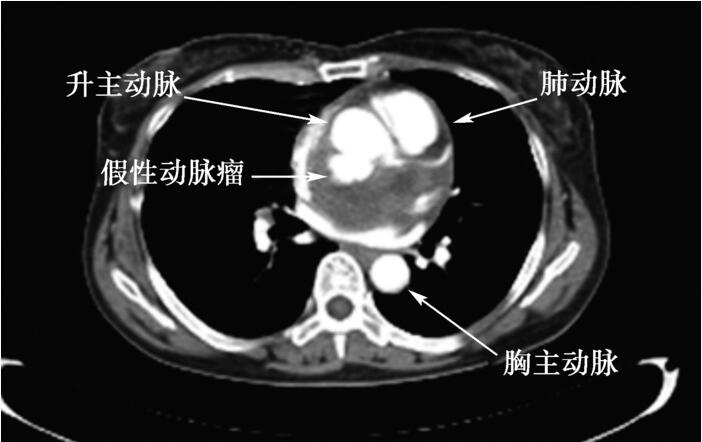

X线胸片:双肺纹理增粗,未见明显浸润、实变影,双肺门不大、纵隔居中、心影饱满稍大,两膈光滑、双侧肋膈角锐利;右前斜位见食管压迹;左前斜位见心后缘与脊柱稍重叠,左主支气管未见抬高,心前缘膨隆,降主动脉与脊柱重叠;结论:心影稍大,左心房、右心室轻度增大可能,请结合临床。胸部CT:升主动脉近段后壁破口、向后突出,见片状稍高密度影,大小4.7cm×6.0cm,平扫CT值约45 Hu,增强扫描可见部分造影剂充盈,相邻血管、左心房受压,破口紧邻左冠窦 (图50-3);胸主动脉内膜光滑,腹主动脉局灶性钙化斑块,腹主动脉分支走行良好,未见异常狭窄、扩张;扫及范围内十二指肠降部向内囊袋状突出影,内见混杂高密度影。结论:升主动脉近段后壁破口、向后突出、假性动脉瘤形成,建议进一步检查;十二指肠降部憩室,憩室内有肠石。

图50-3 胸部CT升主动脉近段后壁破口向后突出、假性动脉瘤形成

本例患者平素体健,4个月前无明显诱因出现胸闷、憋气并于活动后加重,考虑为继发性肺结核、结核性心包炎,予异烟肼、利福平、乙胺丁醇抗结核并穿刺置管引流心包积液。2周前于当地医院行超声心动图偶然发现左心房内占位病变,经食管超声心动图提示主动脉假性动脉瘤可能。到我院就诊后,复查超声心动图提示左心房后上方一混合回声团块,内有2.5cm×1.7cm无回声区,经仔细扫查并增加彩色多普勒,发现无回声区与主动脉后壁破口相通,脉冲多普勒探查到无回声区内收缩期血流信号、峰值流速约98cm/s。此时,主动脉假性动脉瘤诊断基本确立。由于混合斑块体积较大致压迫右肺动脉、左心房和周围组织,加之患者无明确胸部外伤病史,暂不敢贸然下结论,提示假性动脉瘤形成可能性大,不除外占位累及肺动脉主干、右肺动脉可能。进一步行胸部CT提示升主动脉近段后壁破口、向后突出、假性动脉瘤形成,同时排除纵隔占位病变。